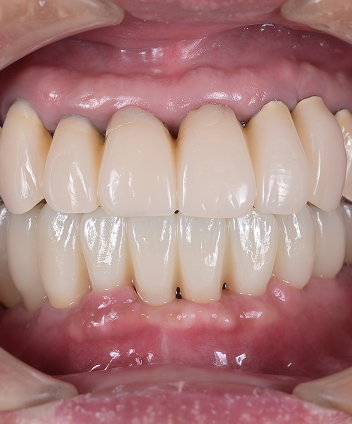

Treatment Case

Treatment

Case